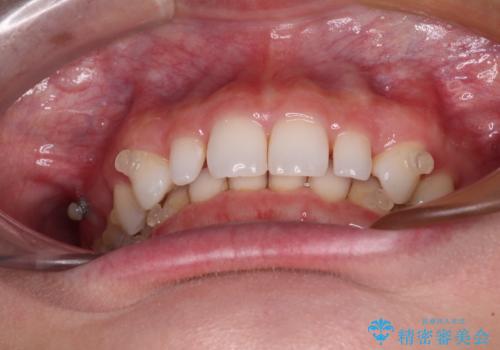

前歯のデコボコと小さい歯を改善 インビザラインとオールセラミッククラウン

- 前歯のデコボコと左右の矮小歯を気にして来院された患者様です。

矮小歯の前後にスペースを作るようにインビザライン矯正治療を計画し、矯正治療後にオールセラミッククラウンによる補綴治療を行うこととしました。

アンカースクリューを用いて上顎歯列全体を後方移動させ、極力過蓋咬合も改善されるよう計画しました。

インビザラインは長時間装着を自己管理する必要がありますが、残念ながら十分な時間の装着を行うことができませんでした。

何とか矮小歯を改善するスペースを作ることはできましたが、過蓋咬合を改善するには至りませんでした。